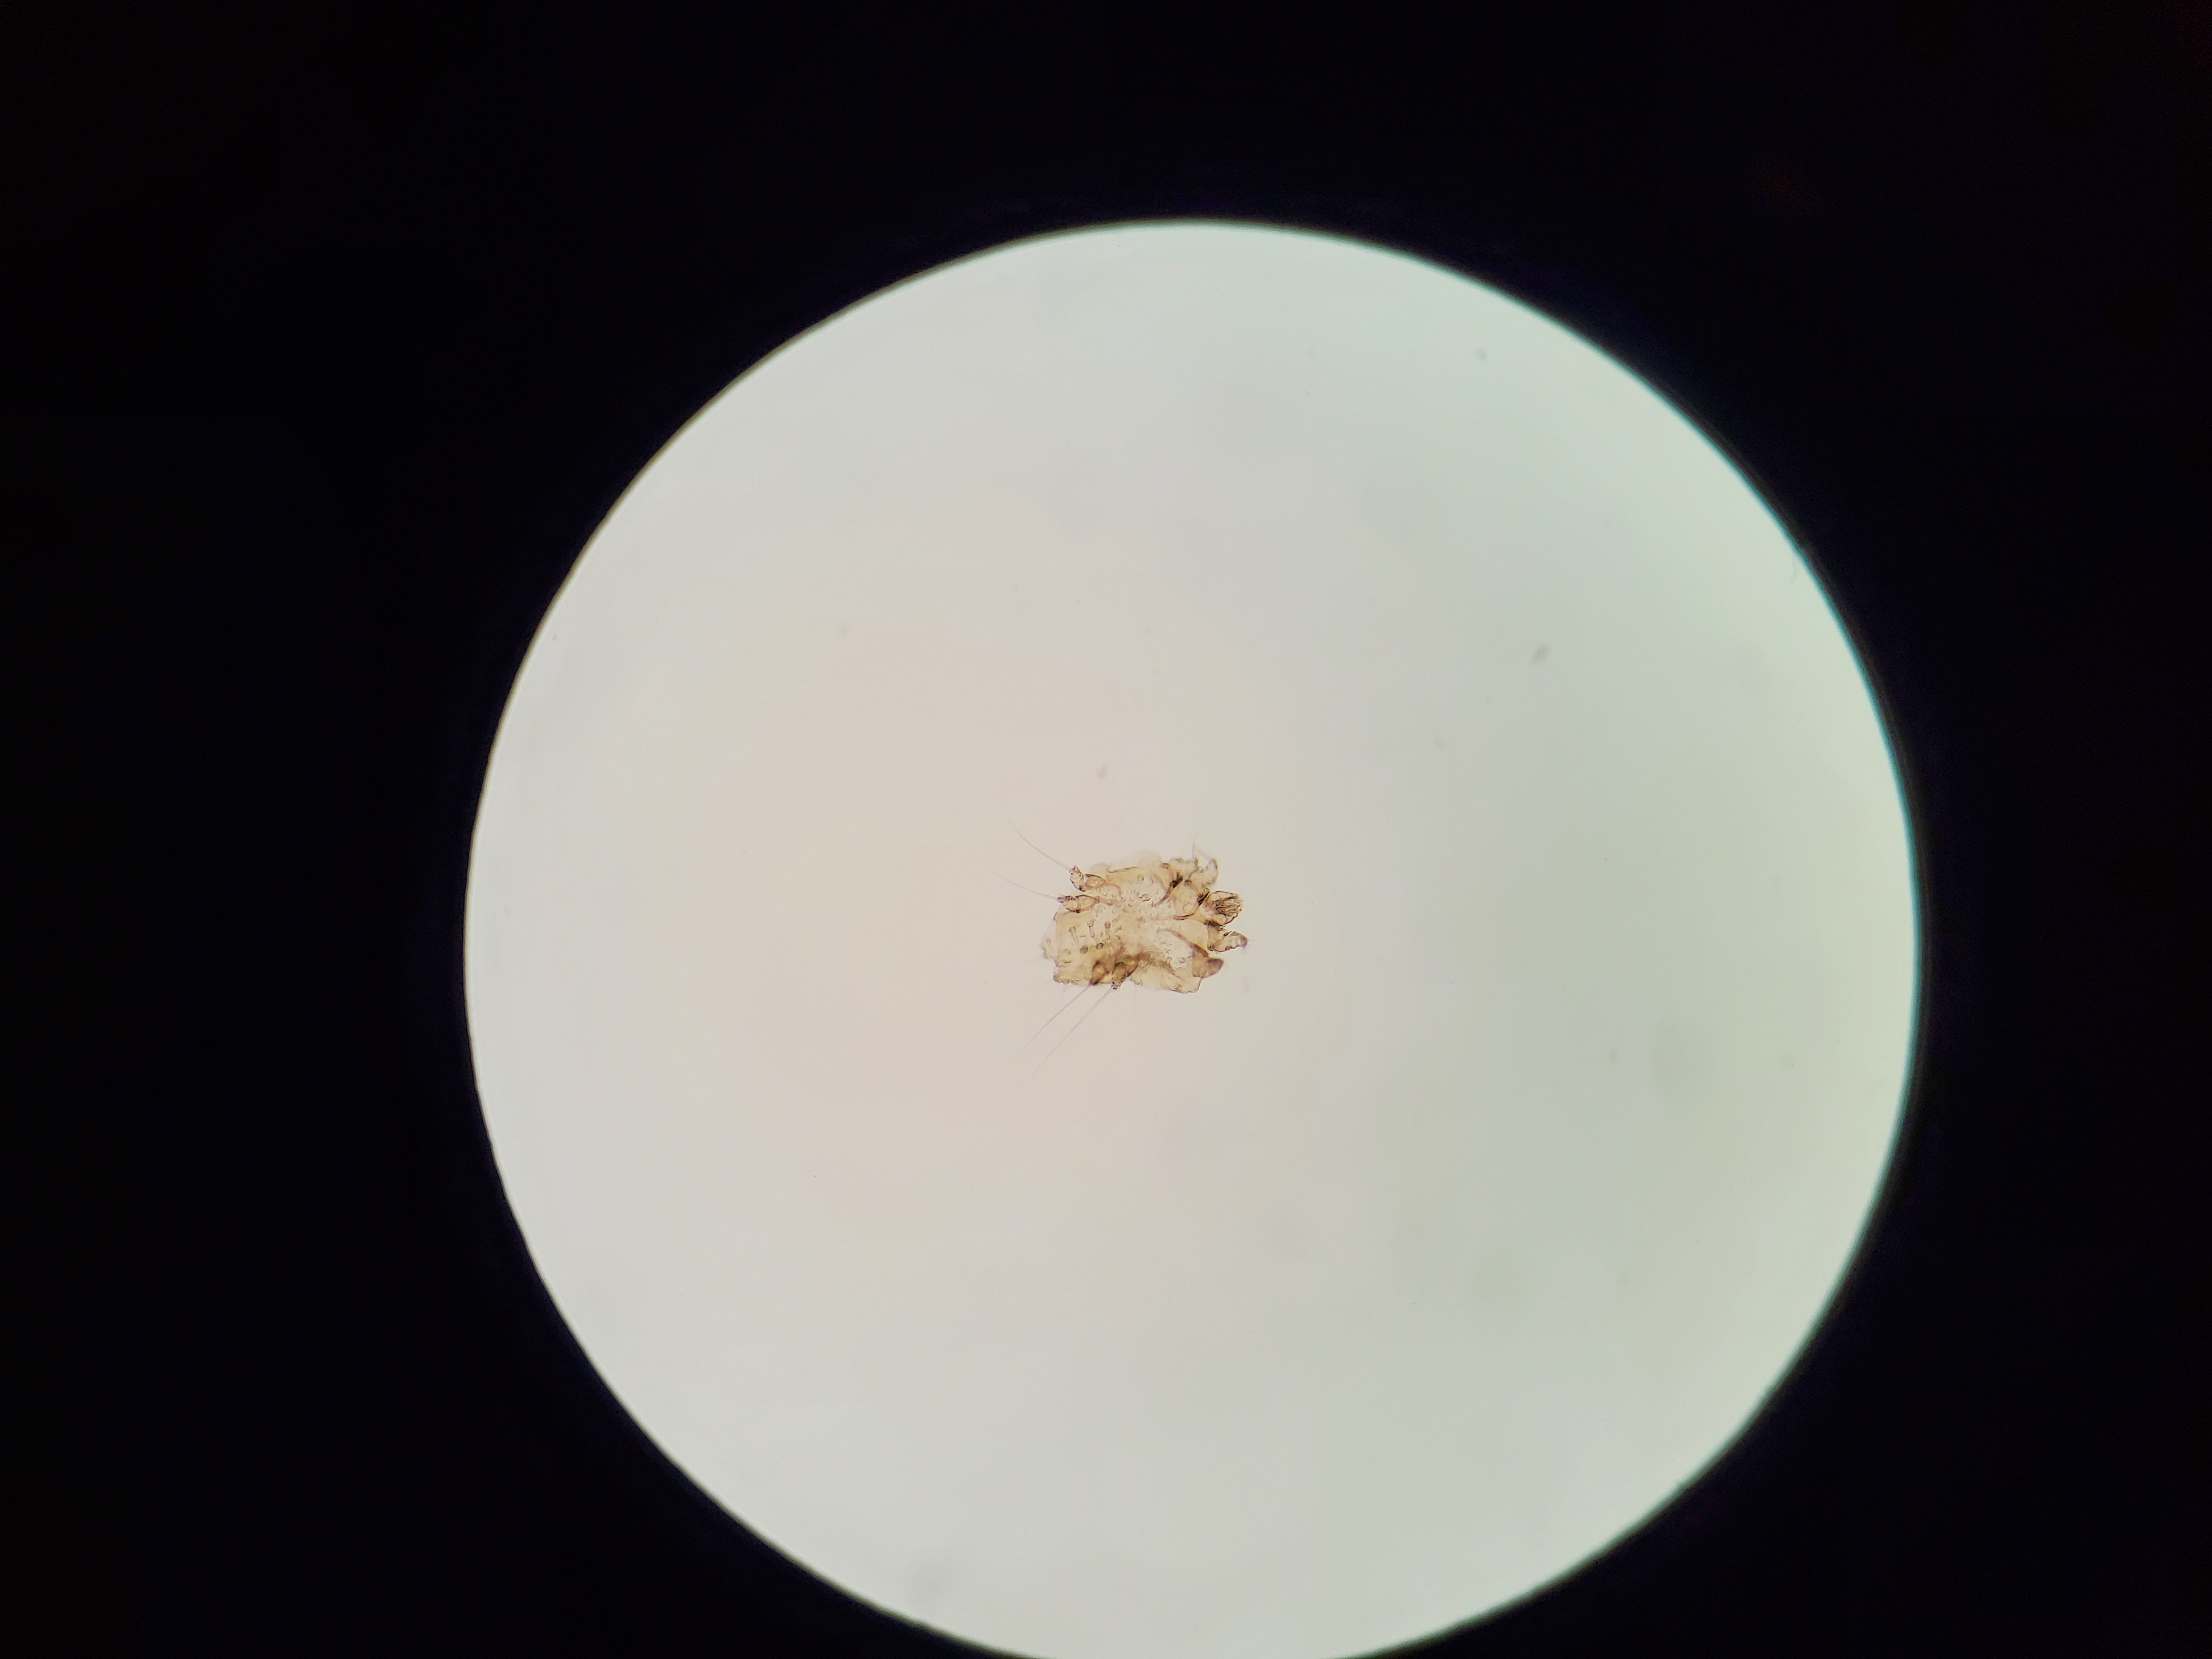

Sarcoptes scabiei

Sample type: Skin